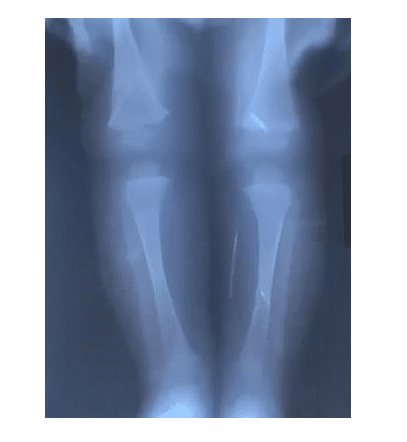

Ο μικρούλης νοσηλεύτηκε το προηγούμενο καλοκαίρι όταν ένας συγγενής ανακάλυψε μια βελόνα μέσα στο στόμα του. Το εννιά μηνών υπεβλήθη σε ακτίνες και εντοπίστηκαν 10 βελόνες. Οι γιατροί προχώρησαν σε αρκετές επεμβάσεις προκειμένου να αφαιρέσουν τα μεταλλικά αντικείμενα από το βρέφος, που έφερε βελόνες σε κρανίο, μύτη, λαιμό, στήθος και πόδια.

Όπως ανέφερε νοσοκομειακή πηγή, κάποιες από τις βελόνες είχαν σκουριάσει μέσα στο κορμάκι του όπου βρίσκονταν για περισσότερους από 3 μήνες. Αμέσως μετά το περιστατικό η μητέρα τέθηκε υπό κράτηση και παραδέχθηκε τις πράξεις της αποκαλύπτοντας και τον λόγο.